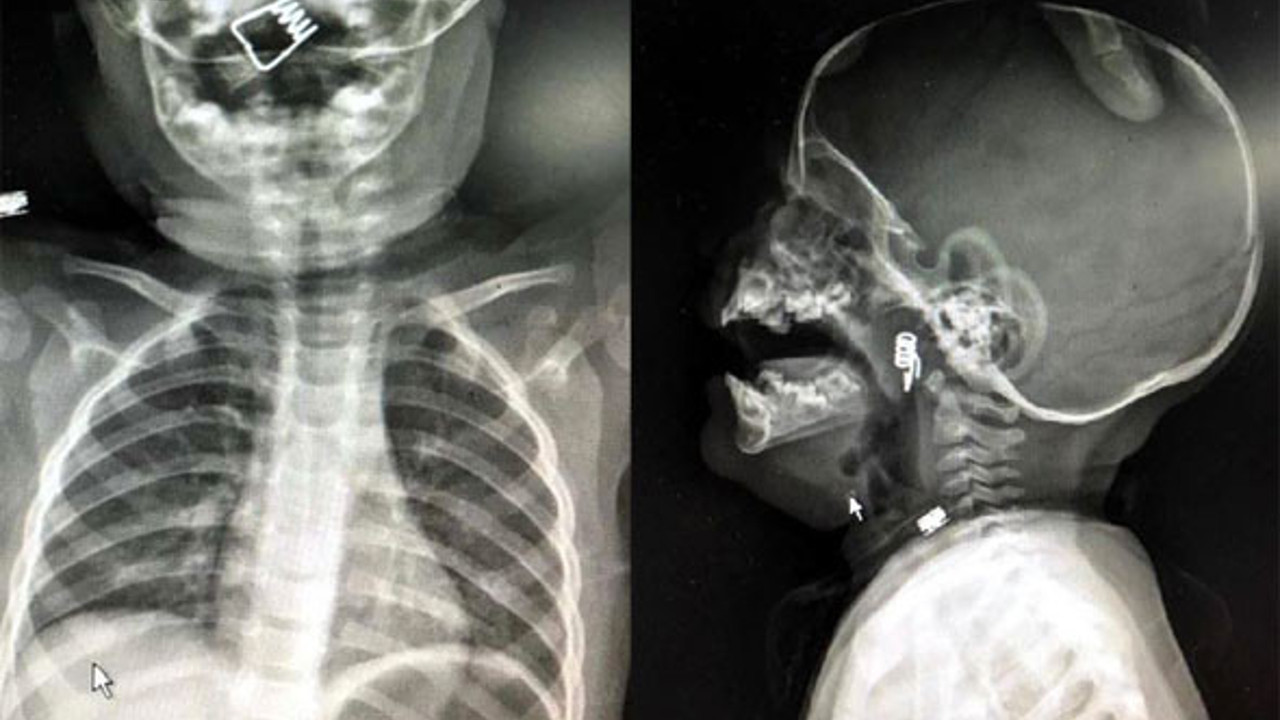

NEVŞEHİR'de inanılması güç bir olay yaşandı. 1 yaşındaki erkek bebek Ö.Y. önüne konulan çamaşır mandalıyla oynarken mandal dağıldı. Minik bebek de mandalın metal yayını hemen ağzına attı. Bebeğin ani tepki verip yutkunması sonrası metal yay, çocuğun boğazına kaçtı. Hastanede çekilen röntgende yayın yeri tespit edildi. Bebeğin nefes borusuna saplanan yay başarılı bir operasyonla çıkarıldı. Nevşehir'de 1 yaşındaki erkek bebek Ö.Y., dün akşam saatlerinde elinde mandalla oynarken, parçalanan mandalın yayını ağzına aldı. Duruma müdahale eden bebeğin babası, yayı çocuğunun ağzından çıkarmaya çalışırken, yay bebeğin genzine kaçarak saplandı. Nevşehir Devlet Hastanesi Acil Polikliniği'ne getirilen bebeği, Acil Nöbetçi doktoru Mustafa Alpaslan muayene ederek gerekli tetkikleri yaptı. Çekilen röntgen filmlerinde mandal yayının lokalizasyonu ve durumu belirlendi. Daha sonra, KBB Uzmanı Op. Dr. Ahmet Cevatzade tarafından yapılan başarılı ameliyat sonucunda bebeğin genzine saplanan mandal yayı çıkartıldı. ANNE BABABALAR AMAN DİKKAT... Operasyonu gerçekleştiren Dr. Cevatzade, ''Özellikle 1-12 aylık döneme karşılık gelen süt çocuğu döneminde bebekler her şeyi ağzına alır. Üzerinde 3 yaş altında kullanılmaması gerektiği yazan ürünlere karşı bazen anne ve babalar pek dikkatli davranmayabiliyor. Bu tarz ürünler boğaza kaçabiliyor. Bu konuda ailelerin küçük çocuklar için yabancı cisim aspirasyonlarına dikkat etmeleri gerekiyor. Nefes borularına kaçacak parçaları uzak tutmaları gerekiyor. Ayrıca 3 yaş altı çocuklarda çerez gibi küçük parçacıklı maddeleri vermemeleri de gerekir. Ağızdan alınan her türlü yabancı cisim hava yolunu tıkadığında hayati tehlike oluşturur'' dedi.